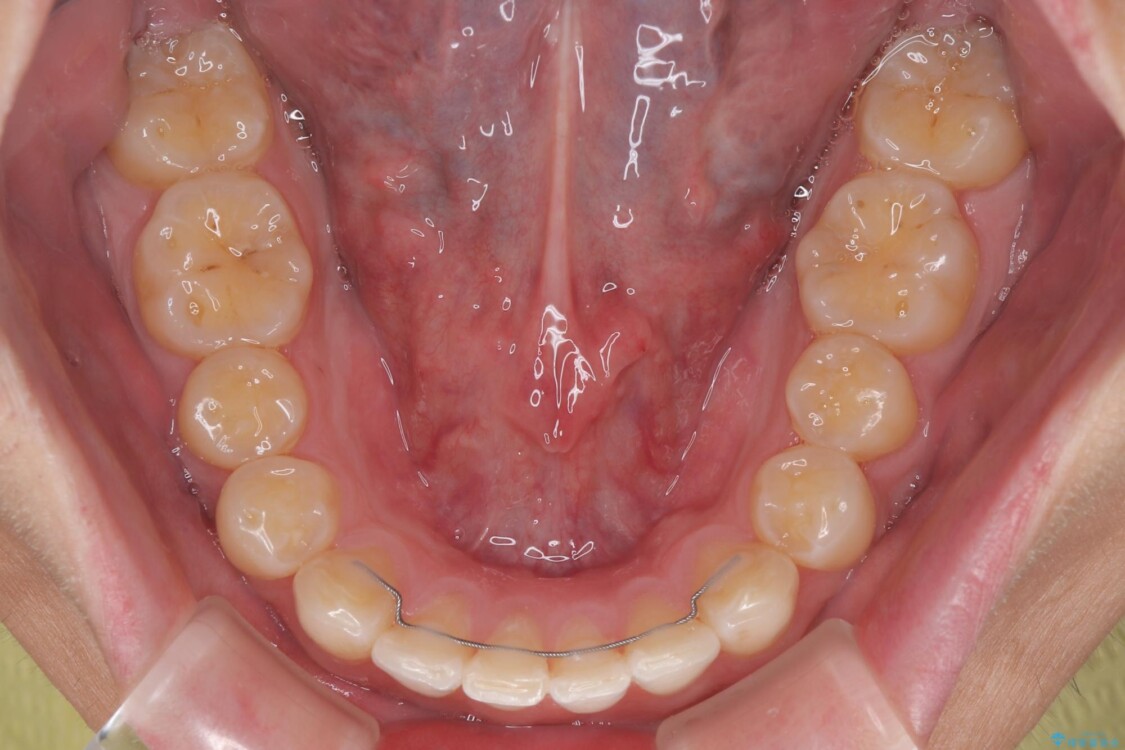

・奥歯のシザーズバイト改善には、口蓋側にアンカースクリュー(TAD)を設置し、矯正用ゴムで内側に牽引

・捻転した第二小臼歯は、ワイヤーと矯正用ゴムの力を用いて正しい位置へ回転移動

治療後

• 前歯のガタガタ・奥歯のかみ合わせ(シザーズバイト)を改善|1年半で完了したメタルブラケット矯正 治療後画像